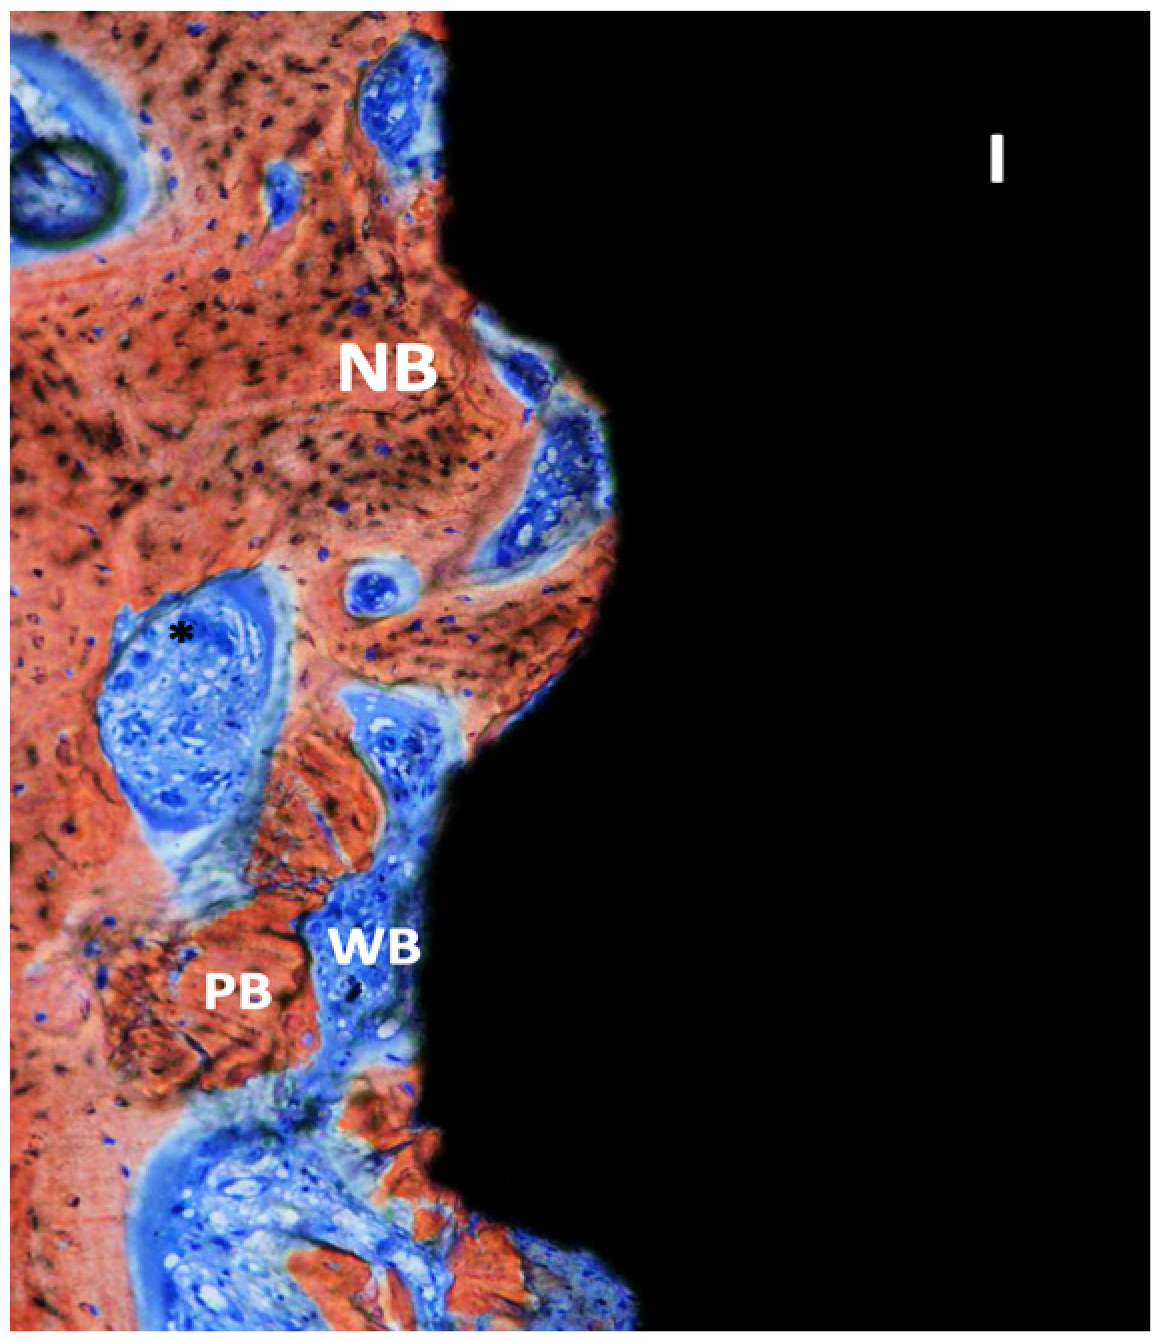

3. Results